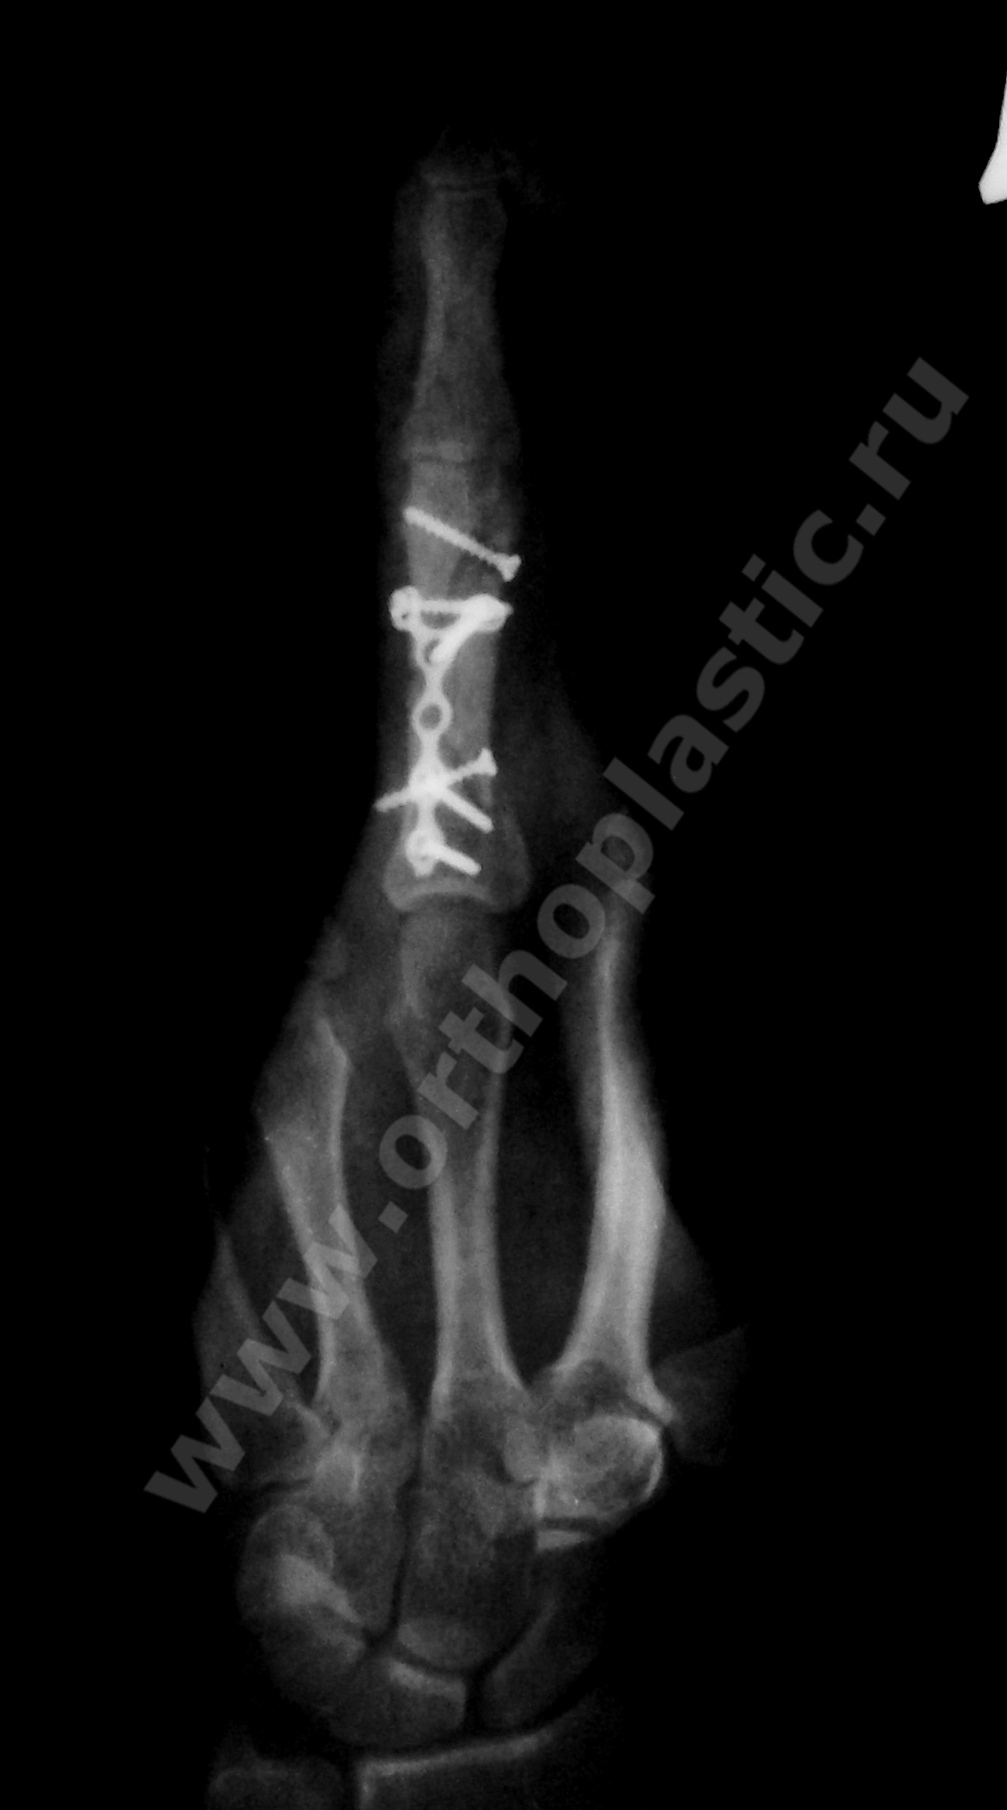

1- малоинвазивный остеосинтез средних фаланг 4, 5 пальцев спицами

2- остесинтез сложного перелома проксимальной фаланги 3-го пальца пластиной и винтами